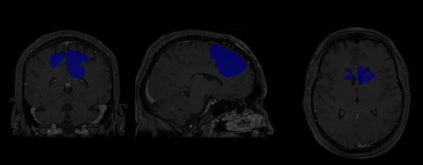

Magnetic Resonance Imaging (MRI) is the most commonly used non-intrusive technique for medical image acquisition. Brain tumor segmentation is the process of algorithmically identifying tumors in brain MRI scans. While many approaches have been proposed in the literature for brain tumor segmentation, this paper proposes a lightweight implementation of U-Net. Apart from providing real-time segmentation of MRI scans, the proposed architecture does not need large amount of data to train the proposed lightweight U-Net. Moreover, no additional data augmentation step is required. The lightweight U-Net shows very promising results on BITE dataset and it achieves a mean intersection-over-union (IoU) of 89% while outperforming the standard benchmark algorithms. Additionally, this work demonstrates an effective use of the three perspective planes, instead of the original three-dimensional volumetric images, for simplified brain tumor segmentation.

翻译:磁共振成像(MRI)是最常用的医学图象获取非侵入性技术。脑肿瘤分解是大脑MRI扫描中算法识别肿瘤的过程。虽然文献中为脑肿瘤分解提出了许多方法,但本文建议对 U-Net 进行轻量应用。除了提供MRI 扫描的实时分解外,拟议的结构不需要大量数据来培训拟议的轻量U-Net。此外,不需要额外的数据增强步骤。轻量U-Net显示BITE数据集非常有希望的结果,它取得了89 % 的平均交叉连接(IOU), 并且超过了标准基准算法。此外,这项工作表明,在简化脑肿瘤分解方面,有效使用了三种视角平面, 而不是原来的三维体量图。